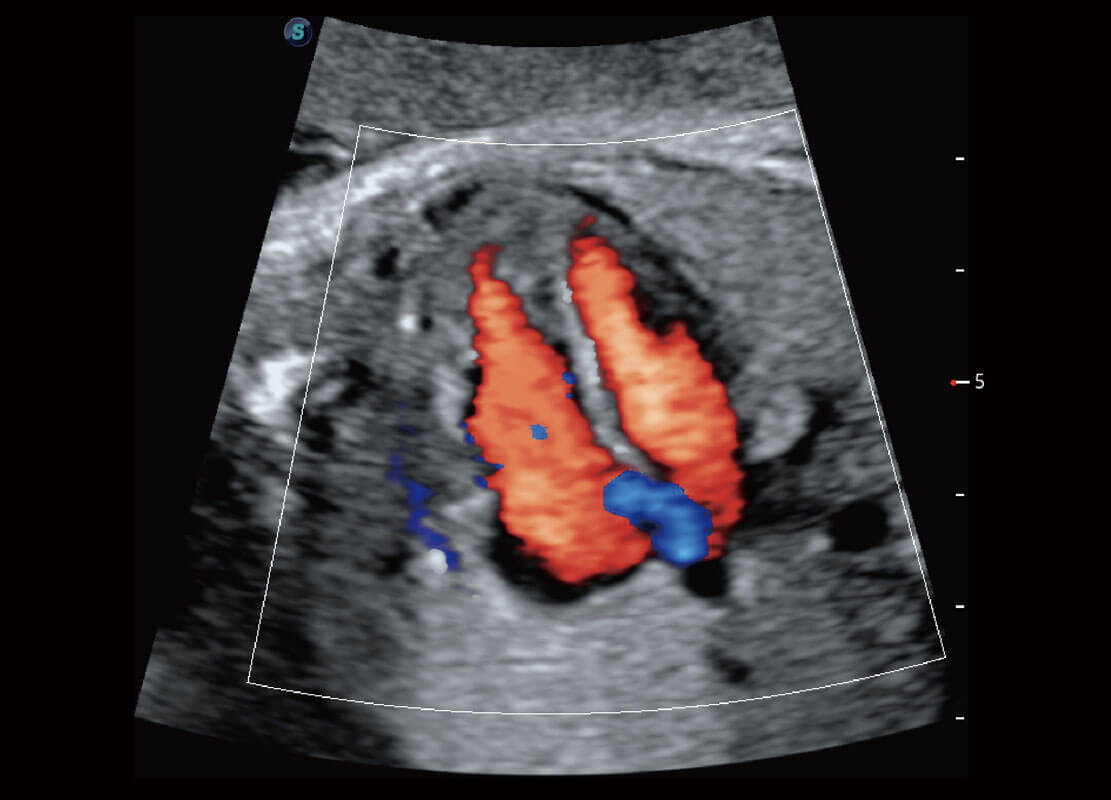

胎儿体循环

P60搭载一系列胎儿心脏成像技术,实现精细的胎儿心脏评估。

四腔心血流